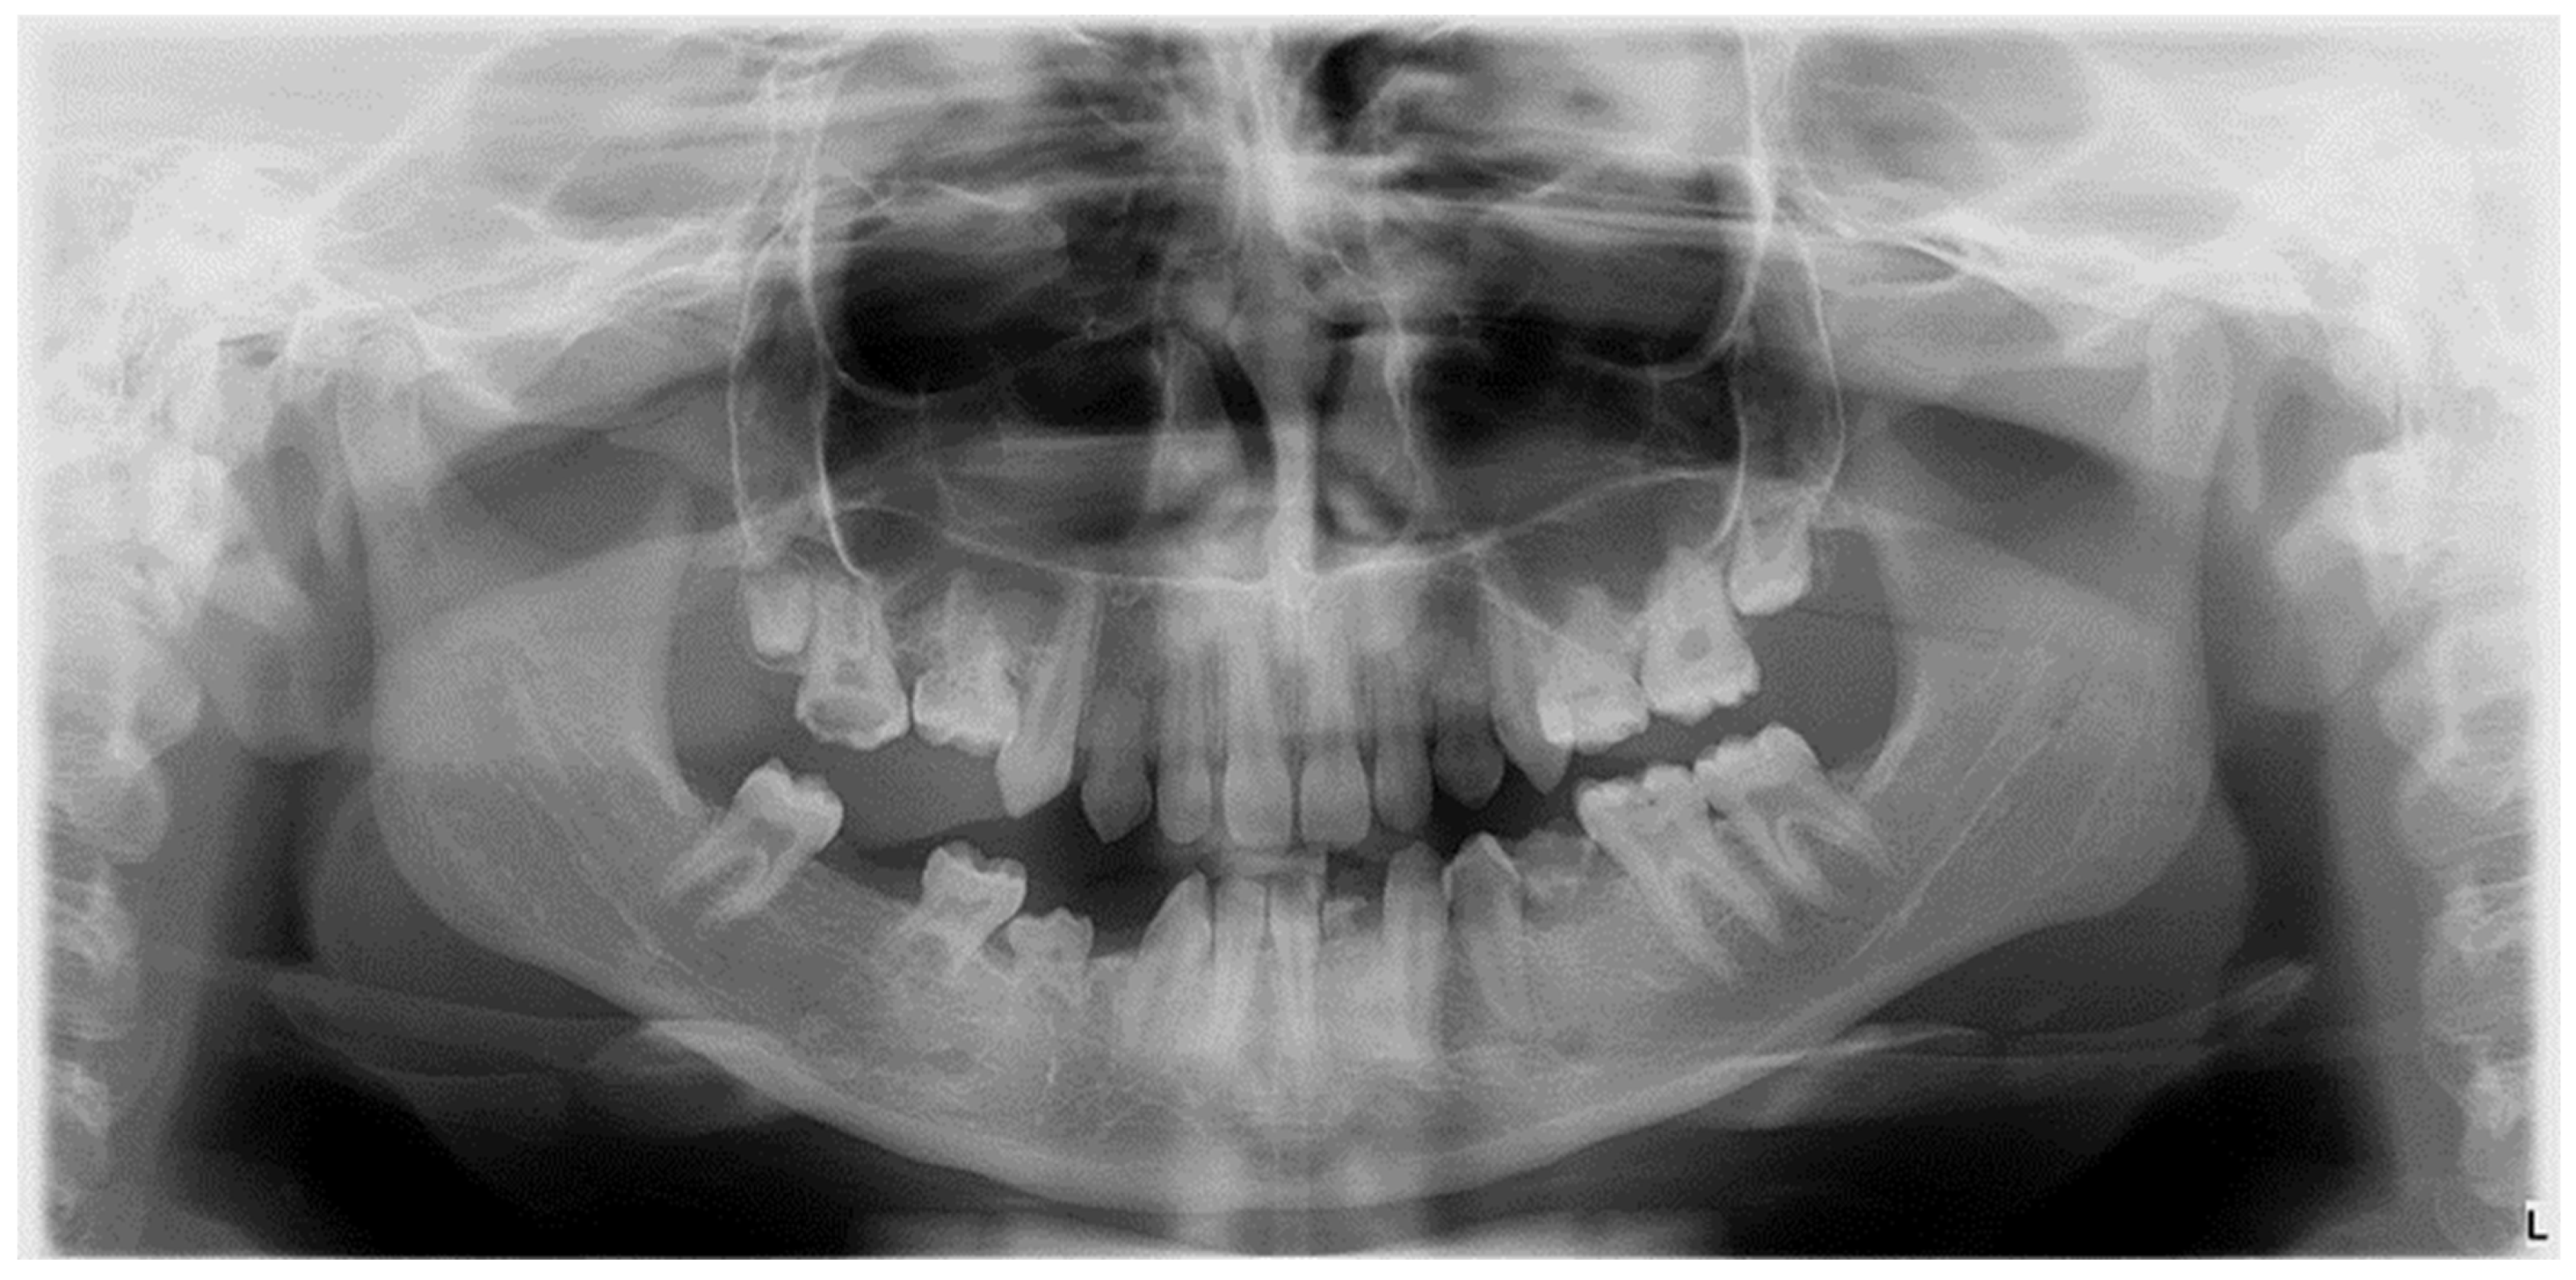

The etiology of DDA is multifactorial, involving hereditary factors, environmental influences, or combinations of these (Figure 1) [3].

Figure 1.

Radiographic image of developmental dental anomalies (number, size, structure).